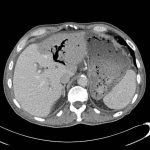

Khí đường mật (Pneumobilia – Aerobilia) là sự hiện diện của khí trong đường mật. Nguyên nhân: Cắt cơ vòng Oddi / Nối mật ruột / Tắc ruột do sỏi mật / Nhiễm trùng đường mật: viêm đường mật, viêm túi mật khí thũng, apxe gan mật…